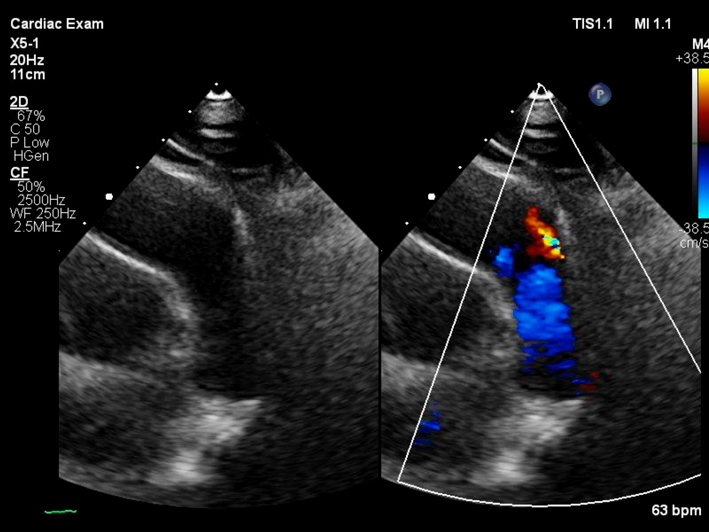

左→右短絡によるQp/Qsは1.2と推定され,心臓カテーテル検査の方針となった.身長168.6 cm,体重71.8 kg,血圧120/66 mmHg,脈拍数76回/分,経皮的酸素飽和度97%,浮腫なし,心拍整,第二肋間胸骨左縁Levine I/VI continuous murmur, bounding pulseなし,呼吸音清,腹部平坦軟,肝脾触知しない.入院時の胸部X線では心胸郭比(CTR : cardio thoracic ratio)47%と心拡大は軽度で,肺血管陰影の増強を認めなかった(Fig. 1).12誘導心電図は洞調律で心拍数60回/分,QRS軸-30°,有意な異常所見は認めなかった(Fig. 2).血液検査では,白血球9,700/µL, AST 28 U/L, ALT 36 U/L, NT-proBNP< 10 pg/mL, LDH 206 U/L, CPK 86 U/Lであった(Table 1).心エコー検査では肺動脈内連続性短絡血流があり(Fig. 3),収縮期max vel=3.7 m/sec拡張期max vel=2.9 m/secであった.また,軽度の僧帽弁逆流を認めた.左室駆出分画73%,左室流入波形(E/A=2.2 E/E′=6.9)と左室機能は保たれていた.明らかな下行大動脈の拡張期逆行性血流は認めなかった.心臓カテーテル検査では,下行大動脈からの造影でPDAはKrichenko A型(Fig. 4)に描出され,ampulla径3.5 mm, PA側2.2 mm,最狭部2.5 mm,長さ8.9 mmであった.Fick法を用いて計算したQp/Qsは1.0,肺血管抵抗値は1.08 Wood単位・m2であった.成人先天性心疾患診療ガイドライン4)に基づき,推奨クラスI,エビデンスレベルCと判断し,初回治療後34年目に再閉鎖目的で入院となった.

Fig. 3 Echocardiography on admission

Parasternal shortaxis view of transthoracic echocardiography showing a continuous left-to-right shunt through the patent ductus arteriosus.